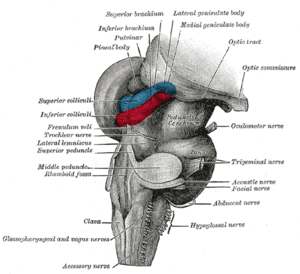

Inferior view midbrain (2), above (3) | |

The midbrain comprises the tectum (or corpora quadrigemina), tegmentum, the cerebral aqueduct (or ventricular mesocoelia or "iter"), and the cerebral peduncles, as well as several nuclei and fasciculi. Caudally the midbrain adjoins the metencephalon (afterbrain) (pons and cerebellum); while rostrally it adjoins the diencephalon (thalamus, hypothalamus, etc.). The midbrain is located below the cerebral cortex, and above the hindbrain, placing it near the center of the brain.[3]

The corpora quadrigemina ("quadruplet bodies") are four solid lobes on the dorsal side of the cerebral aqueduct, where the superior posterior pair are called the superior colliculi and the inferior posterior pair are called the inferior colliculi. The homologous structures are called optic lobes in some lower vertebrates (fishes, amphibians, and birds) where they integrate sensory information from the eyes and certain auditory reflexes.[4][5]

The superior colliculus is involved with saccadic eye movements; while the inferior is a synapsing point for sound information. The trochlear nerve comes out of the posterior surface of the midbrain, below the inferior colliculus.

Cerebral peduncle

The cerebral peduncles are paired structures, present on the ventral side of the cerebral aqueduct, and they further carry tegmentum on the dorsal side and cresta or pes on the ventral side, and both of them accommodate the corticospinal tract fibres, from the internal capsule (i.e., ascending + descending tracts = longitudinal tract.) the middle part of cerebral peduncles carry substantia nigra (literally "Black Matter"), which is a type of basal nucleus. It is the only part of the brain that carries melanin pigment.

Between the peduncles is the interpeduncular fossa, which is a cistern filled with cerebrospinal fluid. The oculomotor nerve comes out between the peduncles, and the trochlear nerve is visible wrapping around the outside of the peduncles. The oculomotor is responsible for pupil constriction (parasympathetic) and certain eye movements.[6]